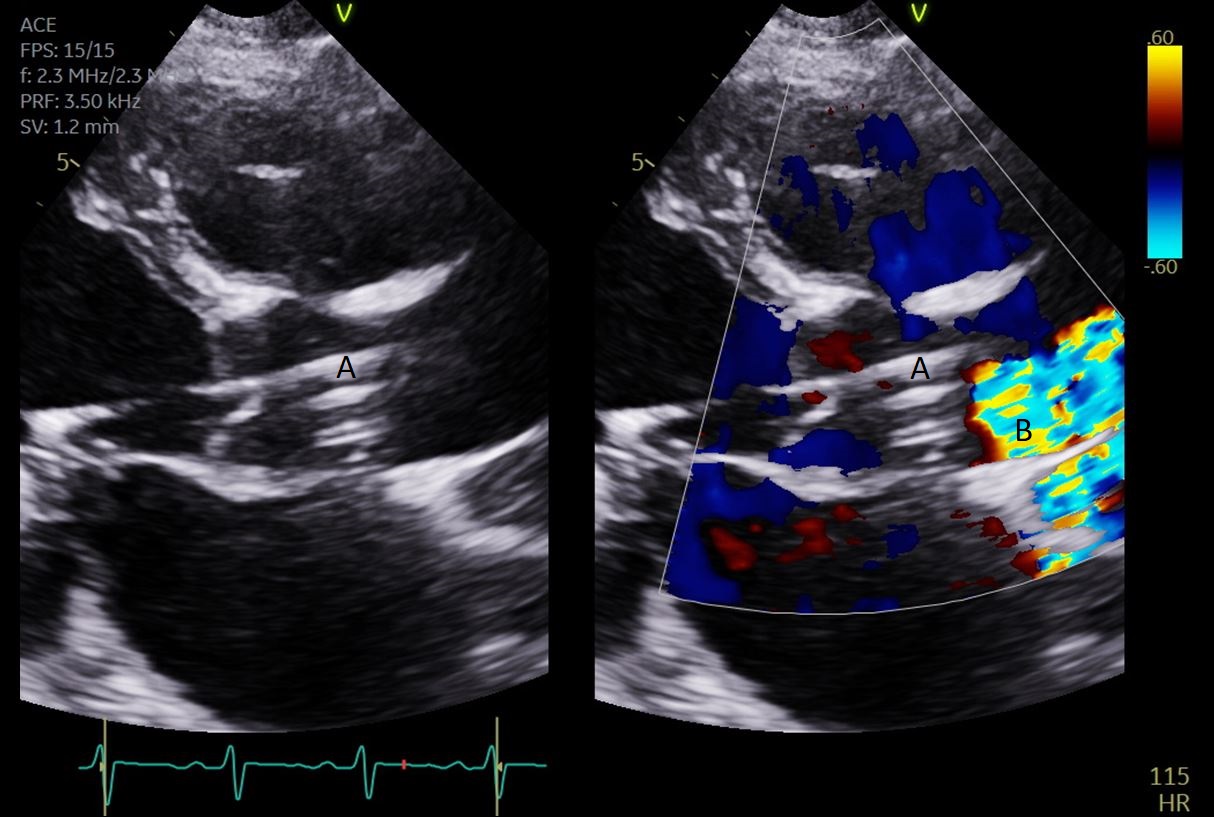

When using TEE, a midesophageal bicaval view can be utilized to assist transseptal puncture [22, 23]. Initially the guidewire is advanced from the femoral vein into the right atrium (RA). The wire is then replaced by a transseptal puncture needle within a catheter tip. This should be angled towards the thinnest part of the interatrial septum (IAS), the fossa ovalis. This can be identified by rotating between the bicaval and the midesophageal aortic valve short axis views. When the transseptal needle is advanced in this location, tenting of the IAS into the left atrium can be visualized and once positioning is confirmed, transseptal puncture can be completed [23]. The catheter is advanced into the left atrium and the needle is exchanged for a guidewire which is positioned in the left upper pulmonary vein. This can be visualized in the mid-esophageal 4 chamber view with the transducer rotated to visualize both left pulmonary veins. Finally, a sheath and dilator are advanced into the left atrium over the guidewire and the inflow cannula is positioned in the left atrium. Utilizing TEE helps lower the risk of complications such as puncturing the aorta or left atrial wall [24]. Additional complications such as tamponade can also be immediately identified if TEE is utilized during the procedure [25]. As noted previously, the arterial cannula is placed in the femoral artery. TEE can be used to confirm guidewire position but cannot visualize the inflow cannula positioning as this is in the iliofemoral artery. Upon activation of the TandemHeart, color flow doppler can help visualize the inflow cannula in the left atrium , as well as confirm that there is no blood being drawn from the right atrium [26].

The TandemHeart Protek Duo is a percutaneous right ventricular assist device (RVAD) placed via a dual-lumen 29 French sheath in the right internal jugular vein. The inflow lumen is situated in the right atrium and outflow lumen in the main pulmonary artery. The port lumens are connected externally to a TandemHeart centrifugal pump [31]. As this is generally placed in the operating room, intra-operative TEE can be used to help guide placement. Similar to the Impella RP, bicaval and midesophageal 4 chamber views can visualize the inflow cannula and RV inflow-outflow view and upper esophageal views can be used to visualize the outflow cannula (Figs. 13,14,15). On occasion, its placement can result in distortion of the tricuspid valve morphology with resultant tricuspid regurgitation (Fig. 16). If this is noted, cannula repositioning can be considered. TEE can also help in identifying the ideal pump speed for a patient on TPD support. When utilizing a “ramp protocol”, where the pump speed is progressively increased intraoperatively, midline interventricular septal position can indicate an appropriate amount of RV support [32].

Fig. 14.Color flow imaging demonstrating a mosaic pattern at the inflow port. The interatrial septum and left atrium are also visualized. Note that no blood flow is being entrained from the left atrium across the inter atrial septum. (A) Left atrium. (B) Inflow port in the right atrium. (C) Mosaic pattern at the inflow port on color flow doppler.